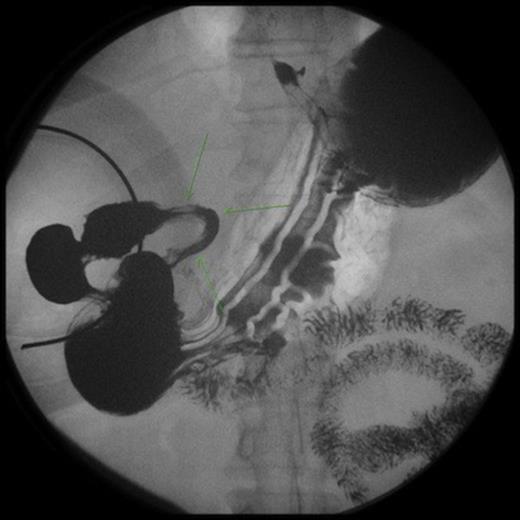

An upper endoscopy showed distal tertiary esophageal contractions, small sliding hiatal hernia with mild gastroesophageal reflux, and an intestinal obstruction at the level of the second portion of the duodenum. The mucosa was normal with the lumen completely constricted. A CT scan demonstrated distension of the stomach and first portion of the duodenum. An UGI study showed severe stenosis of the second portion of the duodenum.